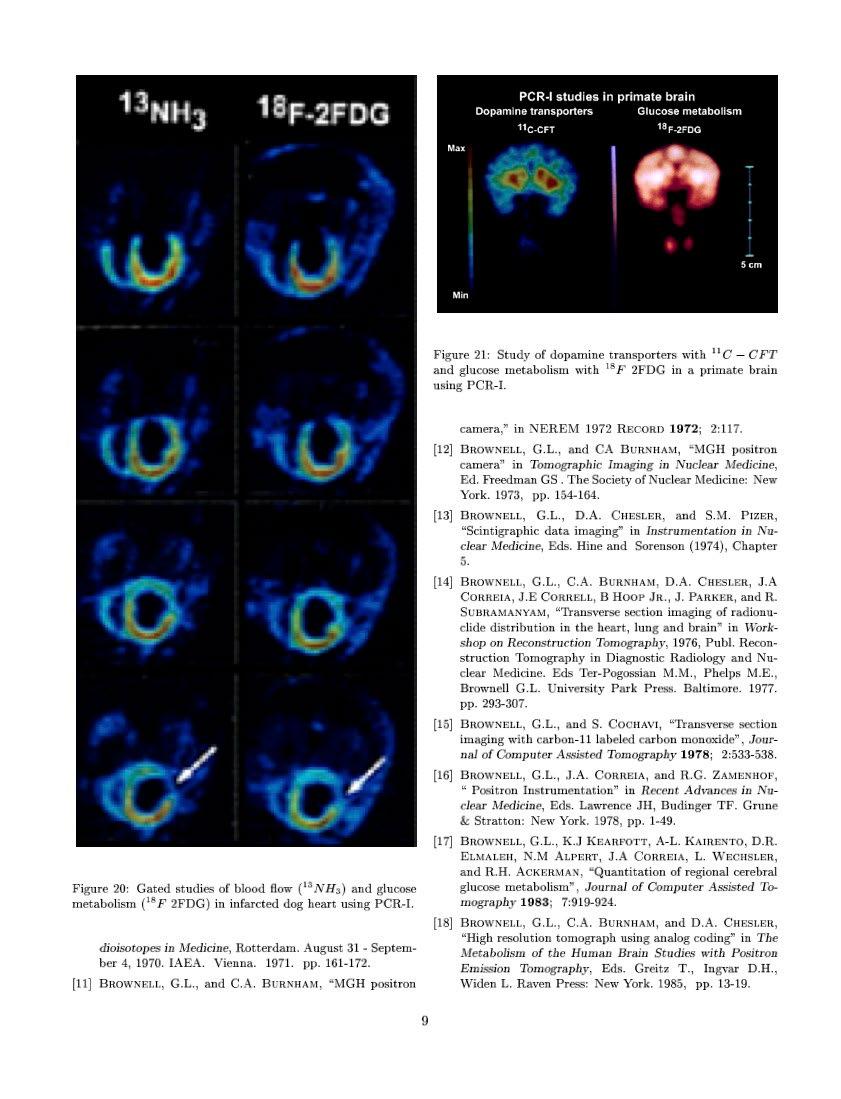

Issuu converts static files into: digital portfolios, online yearbooks, online catalogs, digital photo albums and more. Sign up and create your flipbook.